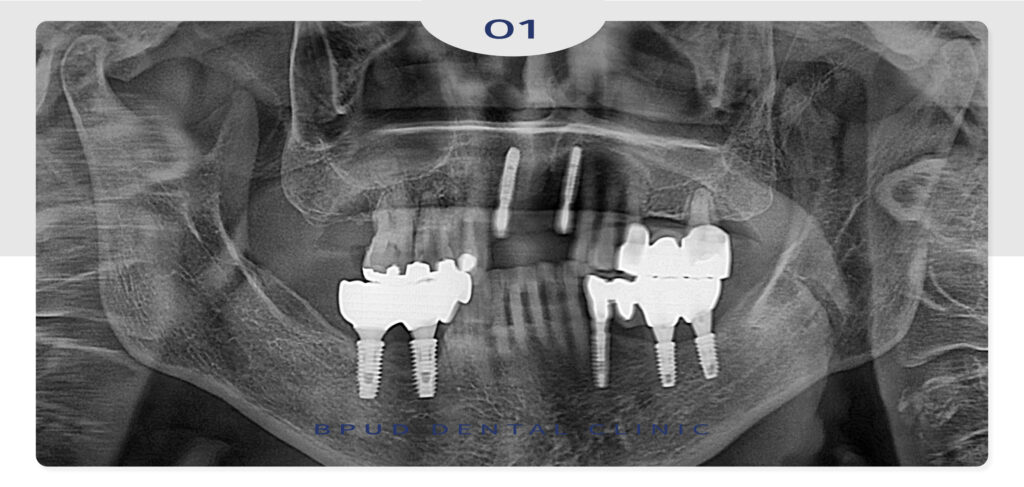

수술 진행 당일, 처음부터 완전히 빠졌던

앞니 부위 치조골 골절이 관찰되어 골이식술을

힘께 진행하였으며 이외 양쪽 송곳니와 작은 어금니에도

충치가 관찰되어 레진치료와 신경치료 후 크라운 수복까지

진행을 하기로 하였습니다.

임플란트 식립 당일의 모습입니다.

앞니는 치조골이 얇고 경사도가 있다 본니

부평동임플란트 시술 자체가 까다로운데요.

주변 치아 구조에 맞춰 각도와 위치를

섬세하게 조정해야 하며, 외관 상 자연스럽게

보여야 하므로 보철도 정교하게 제작해야 합니다.